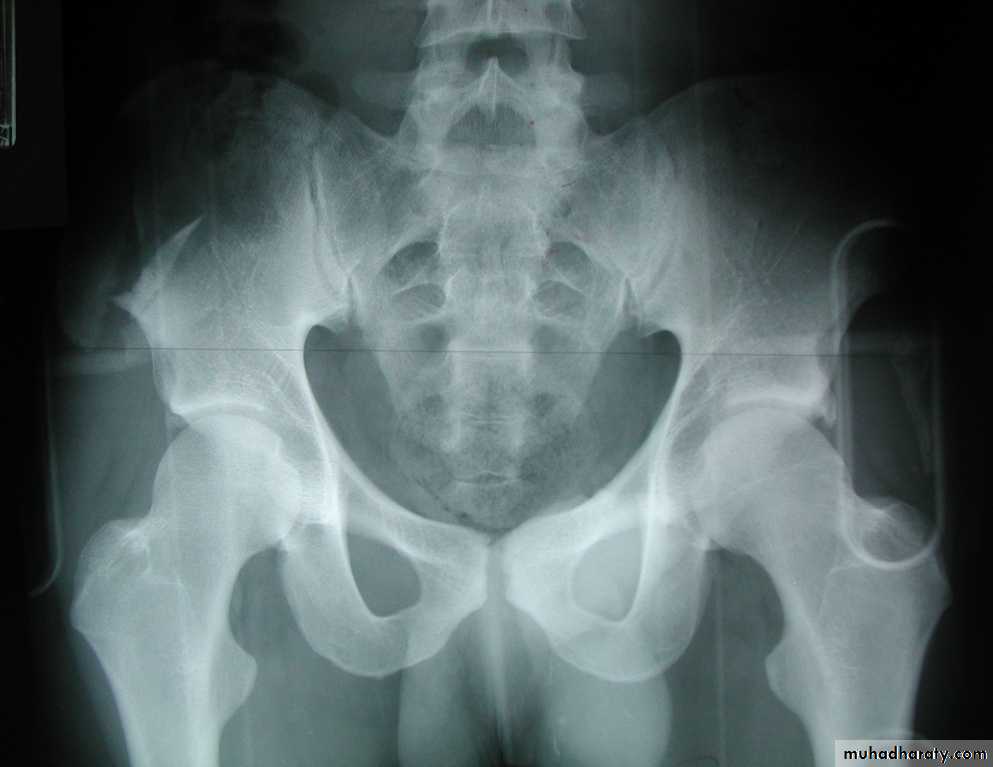

Two types of fracture pelvis .. 1.hemipelvic displacement 2.butterfly fractureabout 10-15%of cases of fractured pelvis have associated urethral inj.

The type of ureth. inj. can often be deduced from the plain radiographThere may be associated inj. to the bladder with either intra or extra peritoneal rupture